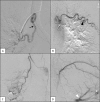

Introduction: Bronchial artery embolisation (BAE) is an established treatment method for massive haemoptysis. The aim of this study is to evaluate the impact of BAE on in-hospital outcomes and long-term survival in patients with massive haemoptysis.

Methods: Retrospective review of all cases of acute massive haemoptysis treated by BAE between April 2000 and April 2012 with at least a 5 year follow up of each patient. Targeted BAE was performed in cases with lateralising symptoms, bronchoscopic sites of bleeding or angiographic unilateral abnormal vasculature. In the absence of lateralising symptoms or signs, bilateral BAE was performed.

Results: 96 BAEs were performed in 68 patients. The majority (64 cases, 67%) underwent unilateral procedures. 83 (86.5%) procedures resulted in immediate/short term control of haemoptysis which lasted for longer than a month. The mean duration of haemoptysis free period after embolisation was 96 months. There were three major complications (cardio-pulmonary arrest, paraparesis and stroke). 38 (56%) patients were still alive at least 5 years following their BAE. Benign causes were associated with significantly longer haemoptysis free periods, mean survival 108 months compared to 32 months in patients with an underlying malignant cause (p = 0.005). An episode of haemoptysis within a month of the initial embolisation was associated reduced overall survival (p = 0.033).

Conclusion: BAE is effective in controlling massive haemoptysis. Long-term survival depends on the underlying pulmonary pathology. Strategies are required to avoid incomplete initial embolisation, which is associated with ongoing haemoptysis and high mortality despite further BAE.